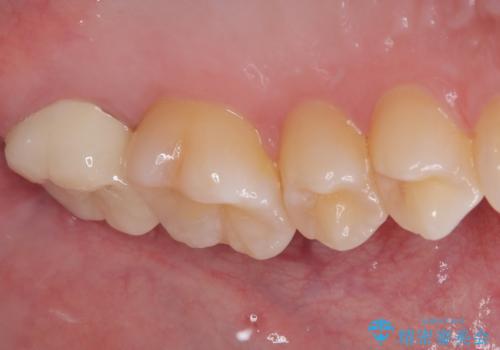

奥歯2歯の間からむし歯が広がったようで、最後方歯は既に神経が失活している状態で、手前の歯は神経組織に問題はないものの速やかに処置が必要な状態でした。

最後方歯は根管治療を行った上でオールセラミッククラウンにて補綴治療を行うこととし、手前の歯はセラミックインレーにて修復治療を行うこととしました。

当院に来院された時には既に痛みはなく、治療終了までスムーズに進めることができました。

今後は定期的にレントゲン写真を撮りながら、根管治療の経過観察を行っていくことになります。